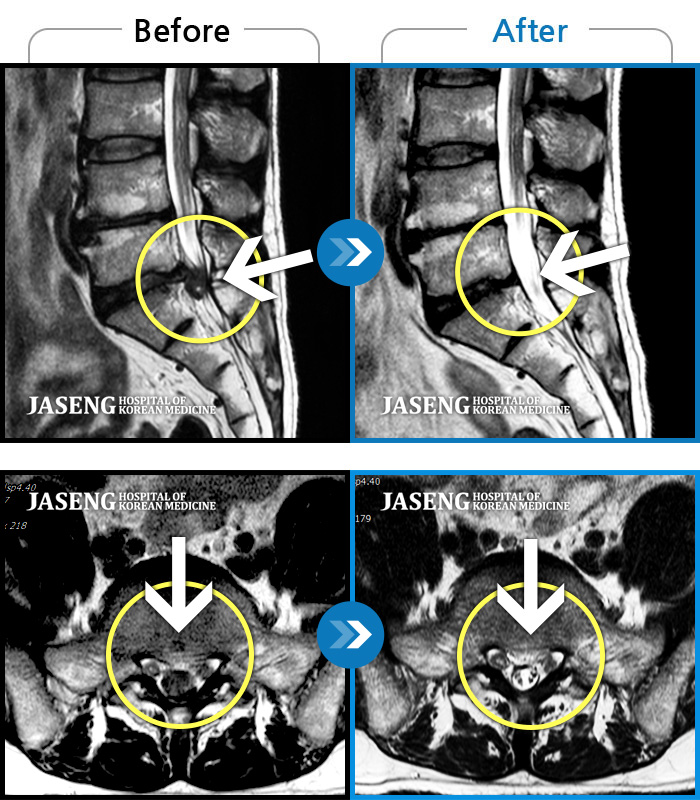

MRI 결과는 추간판협착증 2군데와 추간판탈출되어 터져서 디스크가 좌측으로 흘러내려 좌측 신경을 넓게 누르고 있는 곳이 1군데로 예상보다 심각한 상태였더군요.